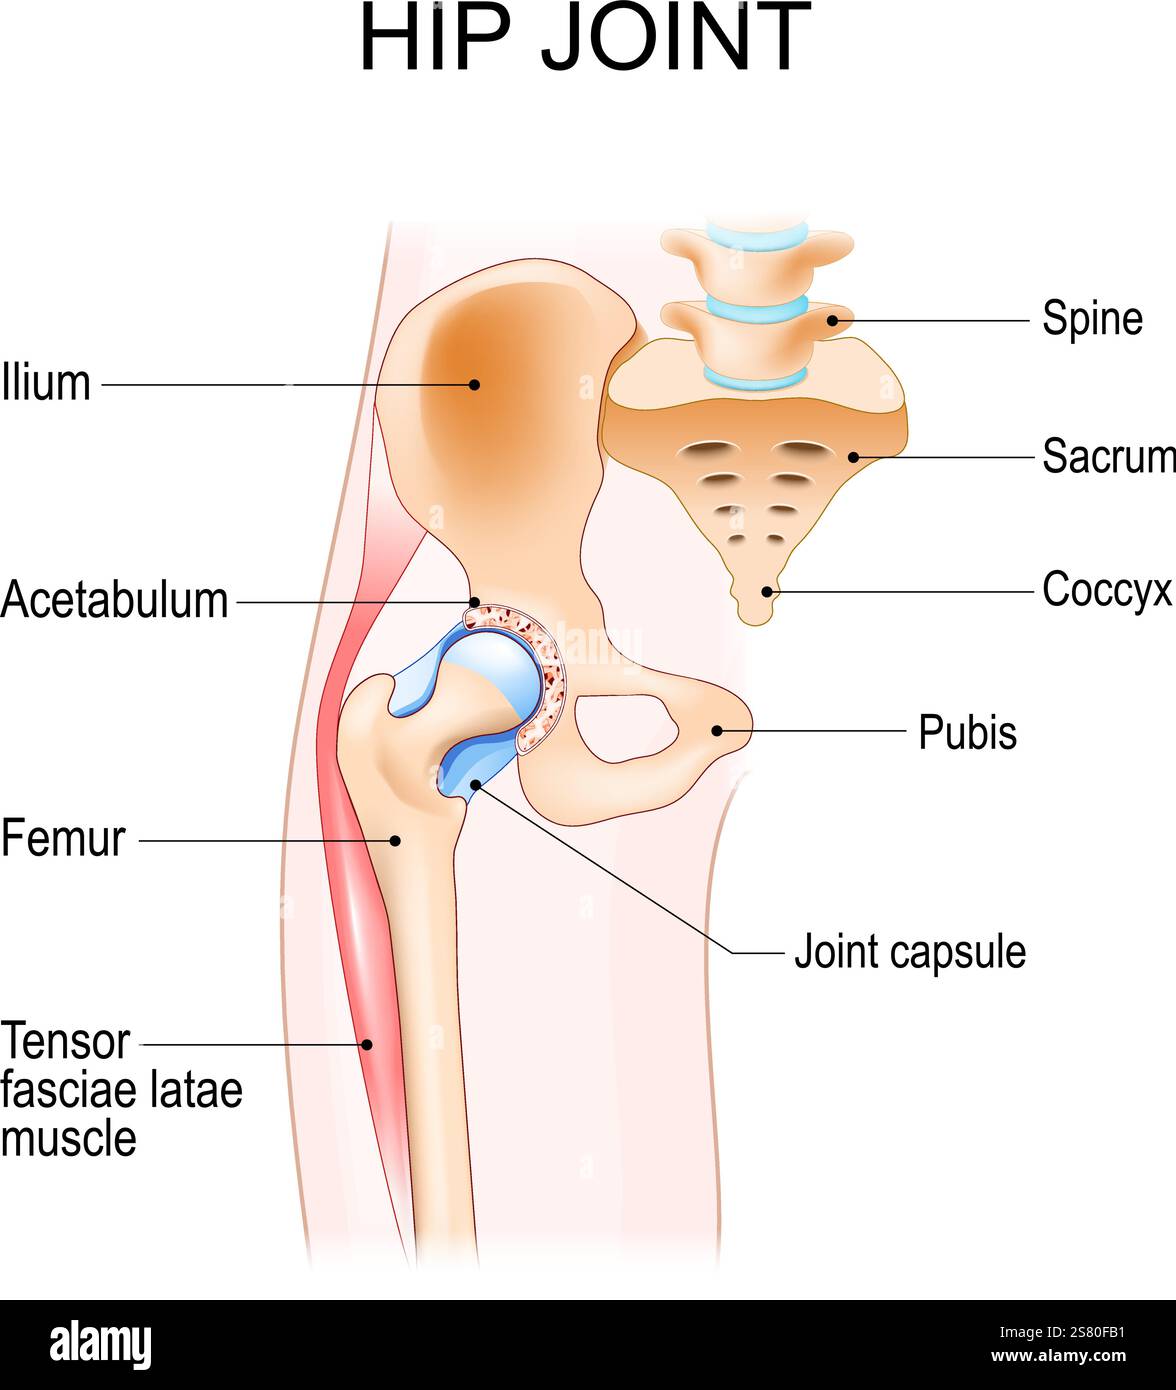

Hip joint anatomy. Ball-and-socket joint. Vector poster Stock Vectorhttps://www.alamy.com/image-license-details/?v=1https://www.alamy.com/hip-joint-anatomy-ball-and-socket-joint-vector-poster-image641712933.html

Hip joint anatomy. Ball-and-socket joint. Vector poster Stock Vectorhttps://www.alamy.com/image-license-details/?v=1https://www.alamy.com/hip-joint-anatomy-ball-and-socket-joint-vector-poster-image641712933.htmlRF2S80FB1–Hip joint anatomy. Ball-and-socket joint. Vector poster